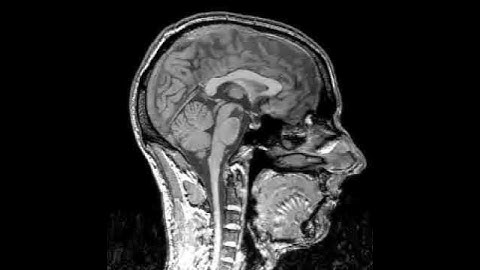

Intro. to fMRI - Wk13, Class2, Pt.1: Applications: reading, and minimally conscious patients